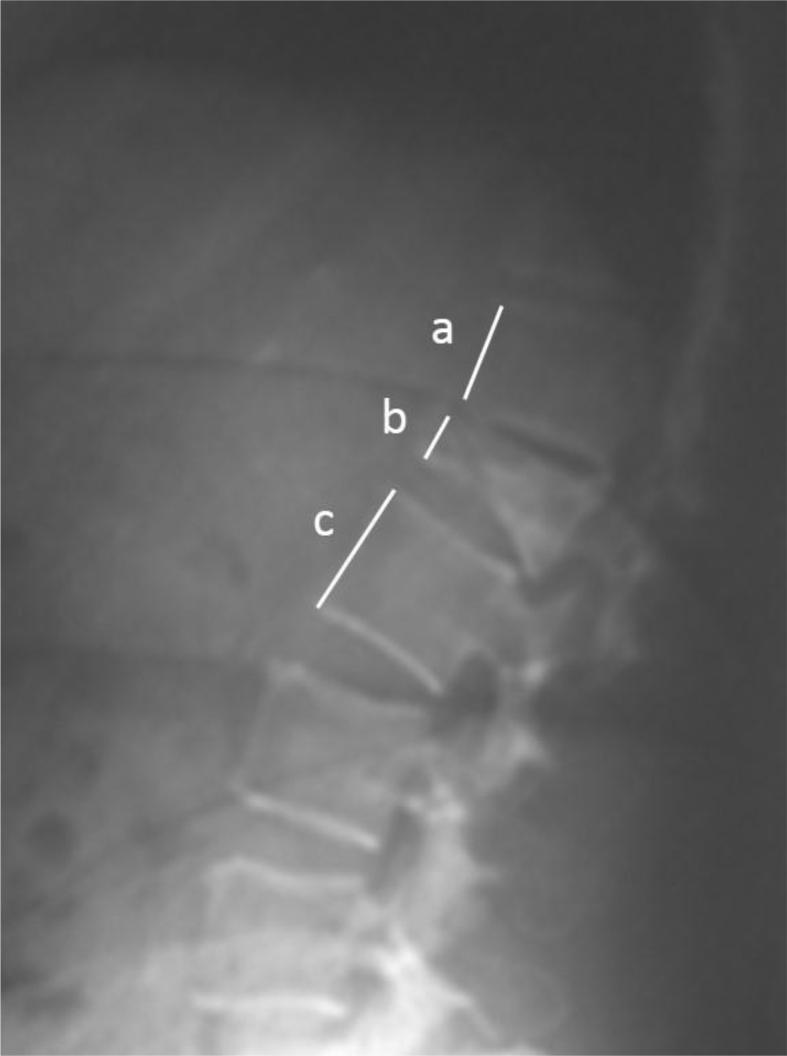

The files of the patients who underwent vertebroplasty or kyphoplasty for osteoporotic vertebrae fractures were retrieved from the archives. Forty-three patients with complete follow-up data were included in the study group. The patients were evaluated for radiological outcomes in terms of local kyphosis angle, wedging index, compression ratio, visual analog pain scale (VAS) and Oswestry Disability Index (ODI).

从档案中检索接受椎体成形术或后凸成形术治疗骨质疏松性椎体骨折患者的病历。研究组纳入了43例有完整随访数据的患者。对患者进行局部后凸角、楔形变指数、压缩率、视觉模拟疼痛量表(VAS)和Oswestry功能障碍指数(ODI)等影像学结果评估。

研究组中,22例患者(17例女性,5例男性;平均年龄:73岁)的24个椎体接受了后凸成形术,而21例患者(16例女性,5例男性;平均年龄:74.7岁)的24个椎体接受了椎体成形术。平均随访时间为26个月。分析两组的VAS和ODI值时,两组术后均显示出统计学上的显著进步。影像学数据显示,后凸成形术组矢状面指数值有统计学上的显著改善,而椎体成形术组则没有。总体并发症发生率为4%。